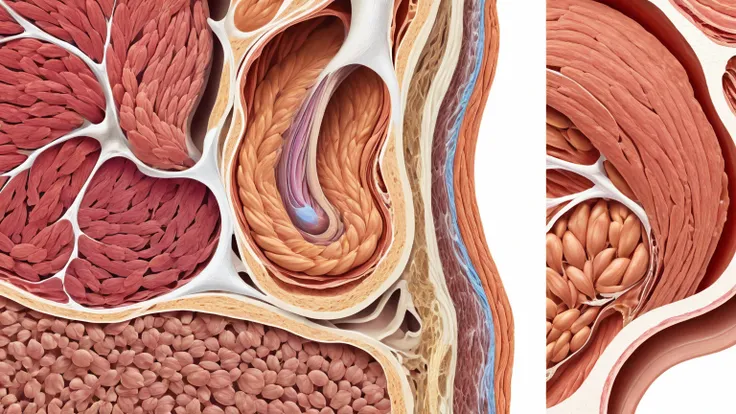

A diagram of the anatomy of the human body

Realice un dibujo de la piel. Coloque las siguientes referencias: Epidermis Fermis Hypodermis Keratinized squamous stratified epithelium Hair Sebaceous gland Sweat gland Pilo erector muscle Connective tissue Blood vessels Nerves Adipocytes

Epidermis Fermis Hypodermis Keratinized squamous stratified epithelium Hair Sebaceous gland Sweat gland Pilo erector muscle Connective tissue Blood vessels Nerves Adipocytes